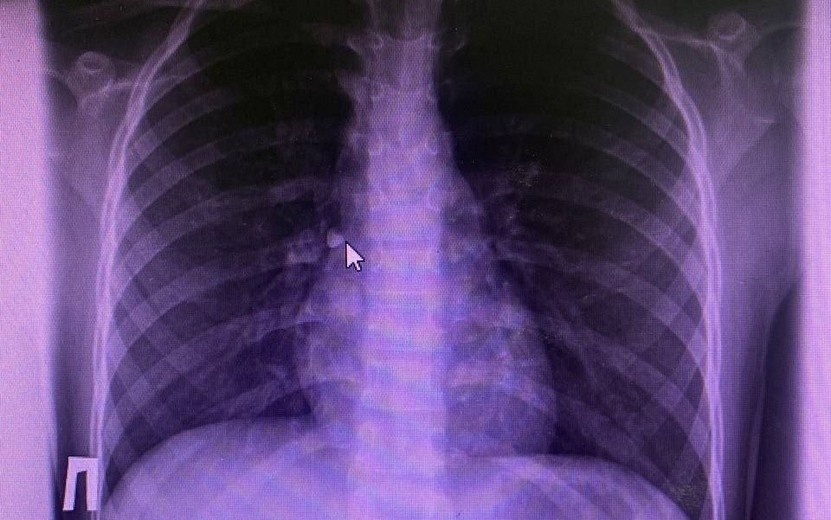

В столице Удмуртии врачи спасли 10-летнюю девочку, которая во время сна случайно вдохнула выпавший молочный зуб. Об этом сообщает пресс-служба регионального Минздрава.

Ребенка экстренно доставили в хирургическое отделение Республиканской детской клинической больницы. Инородный предмет обнаружили в ходе рентгенографического исследования и бронхоскопии. Извлекли зуб из правого главного бронха эндоскопическим способом.